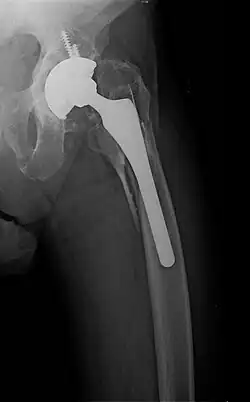

- Periprosthetic fracture – a fracture at the point of mechanical weakness at the end of an implant.

When the initial post-fracture oedema or swelling goes down, the fracture may be placed in a removable brace or orthosis. If being treated with surgery, surgical nails, screws, plates, and wires are used to hold the fractured bone together more directly. Alternatively, fractured bones may be treated by the Ilizarov method, which is a form of an external fixator.

Surgical methods of treating fractures have their own risks and benefits, but usually, surgery is performed only if conservative treatment has failed, is very likely to fail, or is likely to result in a poor functional outcome.[42] With some fractures such as hip fractures (usually caused by osteoporosis), surgery is offered routinely because non-operative treatment results in prolonged immobilisation, which commonly results in complications including chest infections, pressure sores, deconditioning, deep vein thrombosis (DVT), and pulmonary embolism, which are more dangerous than surgery.[43] When a joint surface is damaged by a fracture, surgery is also commonly recommended to make an accurate anatomical reduction and restore the smoothness of the joint.

Sometimes bones are reinforced with metal.[45] These implants must be designed and installed with care. Stress shielding occurs when plates or screws carry too large of a portion of the bone's load, causing atrophy. This problem is reduced, but not eliminated, by the use of low-modulus materials, including titanium and its alloys. The heat generated by the friction of installing hardware can accumulate easily and damage bone tissue, reducing the strength of the connections. If dissimilar metals are installed in contact with one another (i.e., a titanium plate with cobalt-chromium alloy or stainless steel screws), galvanic corrosion will result. The metal ions produced can damage the bone locally and may cause systemic effects as well.